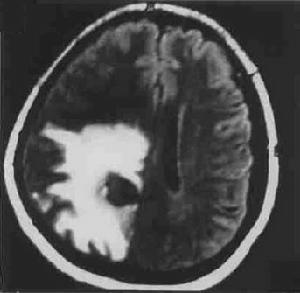

(3)晚期(結核球鈣化結節期):病變呈圓形或卵圓形平掃為高密度影,無腦水腫;增強後呈現“靶征”,即環形強化包繞著中心結節狀鈣化或增強的病灶這是典型的結核球的表現。

2.MRI掃描結核球在T1加權像上為低或略低信號,在T2加權像上大多信號不均勻,表現為低等或略高信號。結核球中心乾酪樣壞死在T2加權像上呈高信號,也可呈模糊不清的同心圓狀分層像,周圍包膜呈低信號,並有高信號的水腫帶環繞。這種有水腫帶包繞者,表明結核球尚未成熟。MRI比CT掃描更能顯示病變的範圍。腦幹的結核球與神經膠質瘤兩者在MRI都表現長T1和短T2,同樣病灶周圍水腫在T2加權像上均高信號,因此,兩者在MRI圖像上不易鑑別。